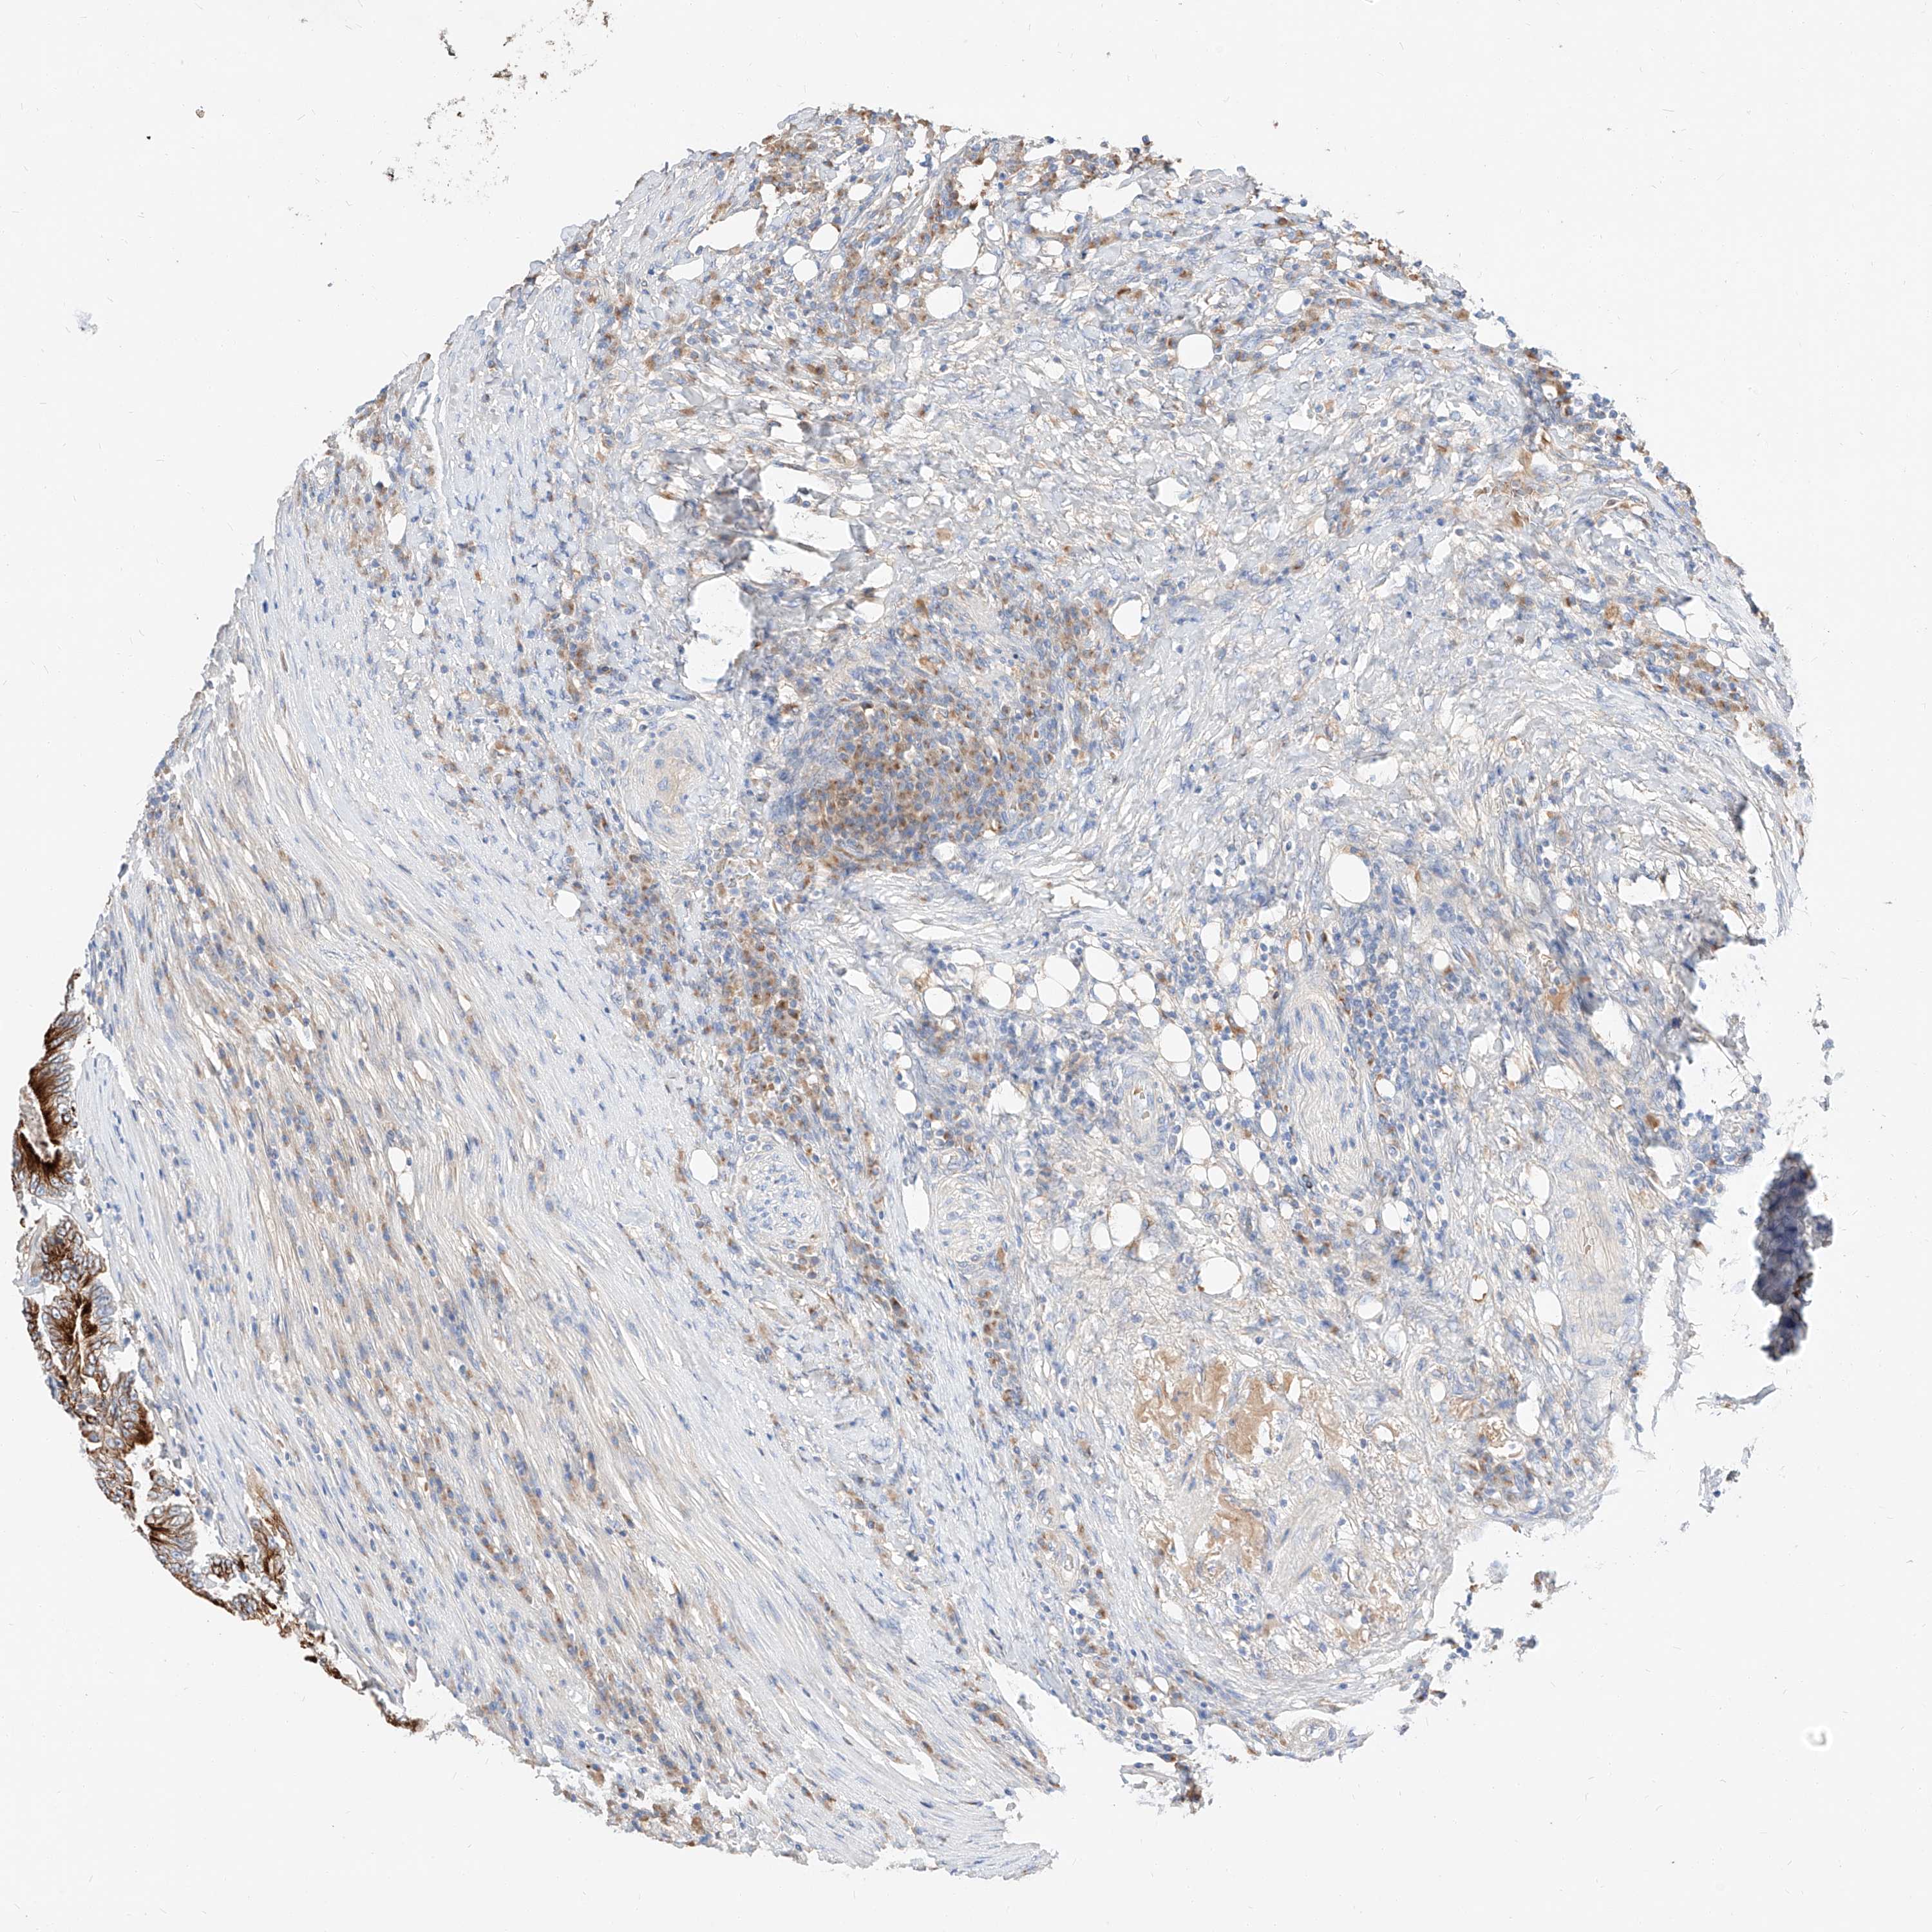

CANCER COLORECTAL CANCER Show tissue menu

ANTIBODIES

AND

VALIDATION